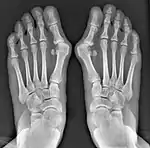

- For recurrence correction after osteotomy procedure (Fig. 8)

Late deformity recurrence can happen after osteotomy (bone-breaking) procedures because osteotomy surgeries do not specifically stabilize first metatarsal bone.